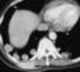

Renal cell carcinoma metastasis to lung

Renal cell carcinoma (RCC) is a kidney cancer that originates in the lining of the proximal convoluted tubule, a part of the very small tubes in the kidney that transport primary urine. RCC is the most common type of kidney cancer in adults, responsible for approximately 90–95% of cases. [Source: Wikipedia ]